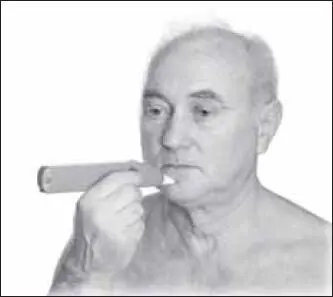

Известной «антистрессовой» точкой является точка ди-хэ (расположена в подбородочной ямке, при пальпации там чувствуется пульсация) (рис. 138).

Воздействие проводится чаще всего 1-м пальцем. Фиксируя точку концевой фалангой, производят резкое надавливание в течение 2–3 секунд. Действие повторяют по 10–15 раз, достигая эффекта расслабленности, релаксации.

Для более точного нахождения точек используют аппараты электропунктуры, измеряющие электрическое сопротивление поверхности тела (биологически активной точке соответствует низкое сопротивление) (рис. 139).

Когда электрод касается точки, подается звуковой или световой сигнал или максимально отклоняется стрелка на шкале.